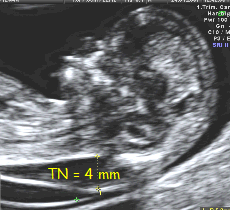

- Espinha bífida aberta é associada à Malformação de Arnold-Chiari II com deslocamento caudal do tronco cerebral (brain stem – BS) e obliteração da cisterna magna.

- Com 11-13 semanas, no corte sagital médio da cabeça, a parte inferior do cérebro entre o osso esfenoide anteriormente e o osso occipital (occipital bone – OB) posteriormente, pode ser dividida em tronco cerebral anteriormente e uma combinação de 4o ventrículo e cisterna magna posteriormente. Na maioria dos casos, o diâmetro do tronco está aumentado, a distância entre o tronco e o osso occipital (“BSOB”) está diminuída e a razão BS/BSOB é >1.0 .